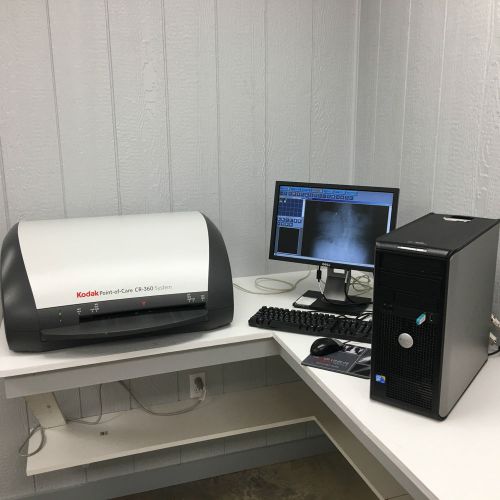

2009 Kodak Point of Care 360 digital CR Reader